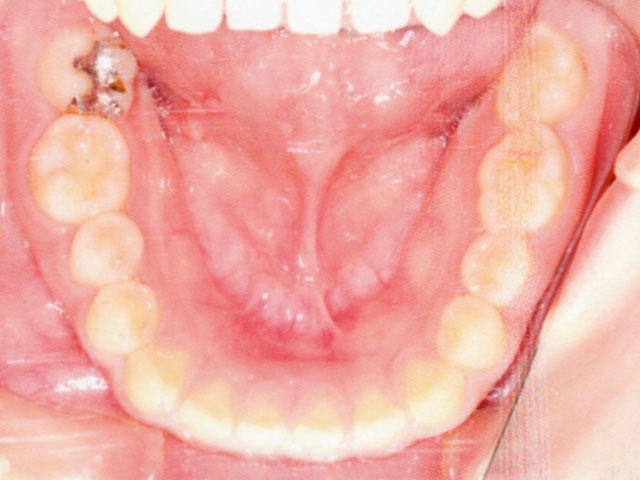

症例02【空隙歯列】

16歳9か月(男子)

上下の顎の成長・発育のバランスには問題はなく、骨格的な不調和は認められませんでした。

ただし、歯の大きさが平均よりもやや小さいことに加え、舌で前歯を押し出す癖(舌突出癖)がみられ、これが前歯の位置に影響している状態でした。

そのため、治療計画は非抜歯とし、スタンダードエッジワイズ法による矯正治療を選択。

- 空隙歯列